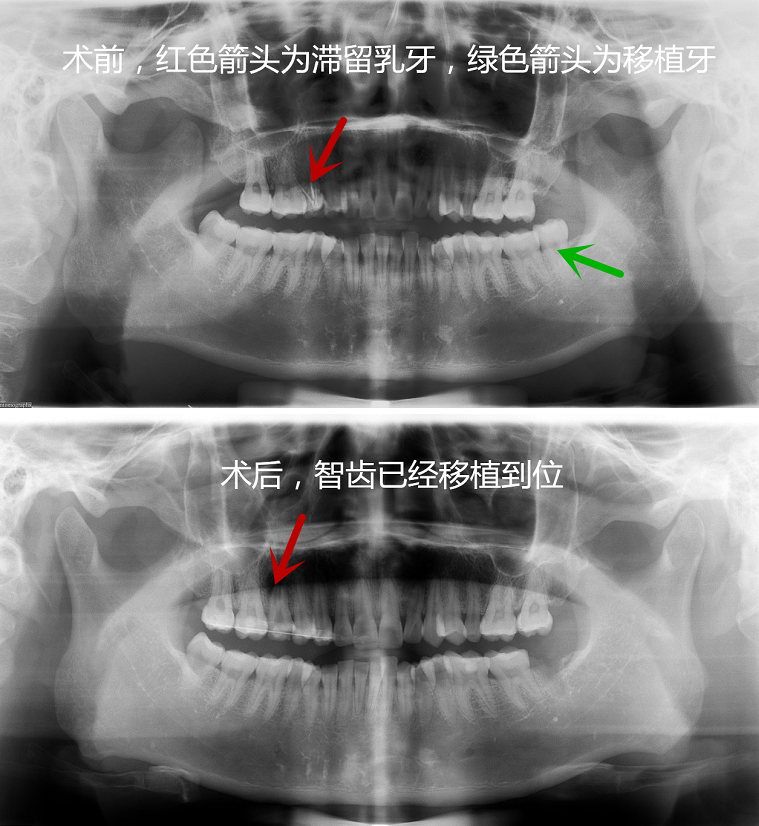

智齿该不该拔 智齿拔除需注意哪些方面